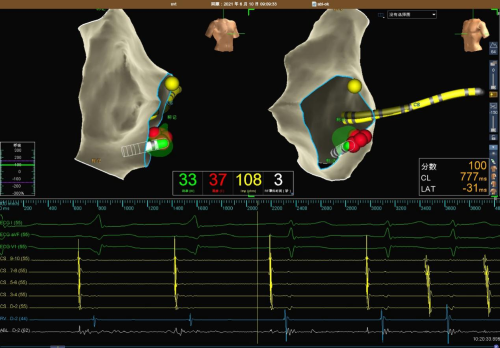

在三维系统的帮助下,张勇华医生成功找到靶点,消融3秒后预激消失。因旁道位置较深,预激波多次恢复,于靶点附近高功率消融3秒预激波消失,在靶点附近巩固消融3分钟,观察20分钟不再恢复,手术顺利结束,术后观察再无心室预激。

张勇华医师穿刺房间隔后送消融导管到左房,在三维系统下找到消融靶点,放电消融2秒,旁道传导很快消失,在靶点处巩固消融120秒,手术取得圆满成功,一共用时仅35分钟。什么是室上性心动过速?